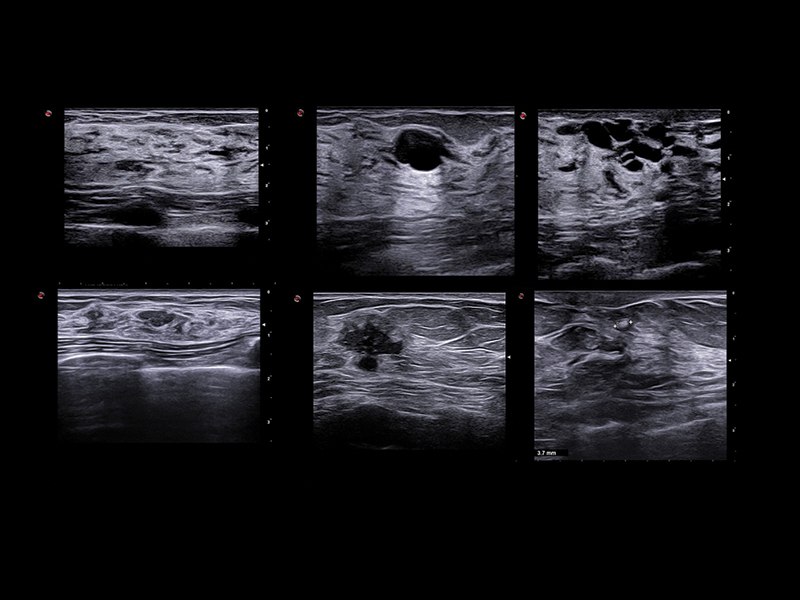

Clinical Images

Breast clinical image